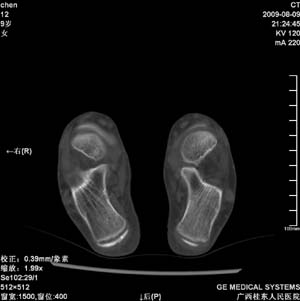

标题: PED2867:右侧内踝肿胀,骨质改变,请各位老师会诊 [打印本页]

标题: PED2867:右侧内踝肿胀,骨质改变,请各位老师会诊

九岁小朋友,近期左侧内踝疼痛,局部肿胀,平时无特殊,近期经常溜干冰

对不起,是右侧内踝肿胀

双踝关节骨质及发育未见异常。

左侧内踝密度增高,请结合临床!